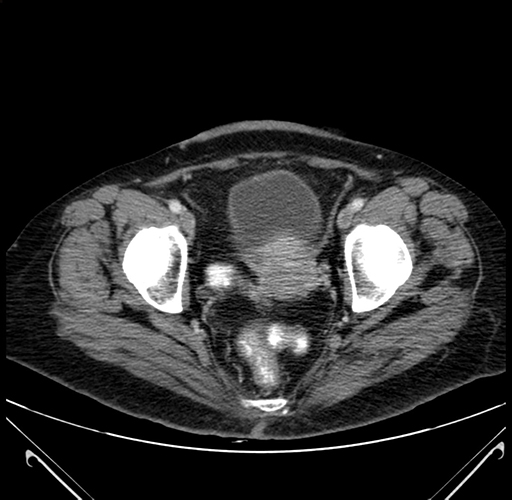

Pre-Chemo: Axial Venous